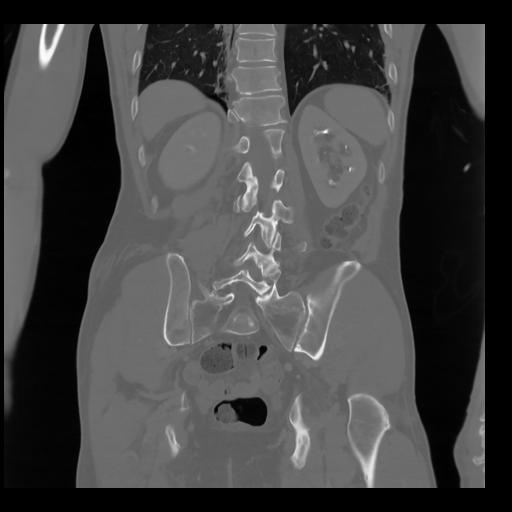

35 CUERPO,CE,Coronal,3.000,CUERPO,Coronal,